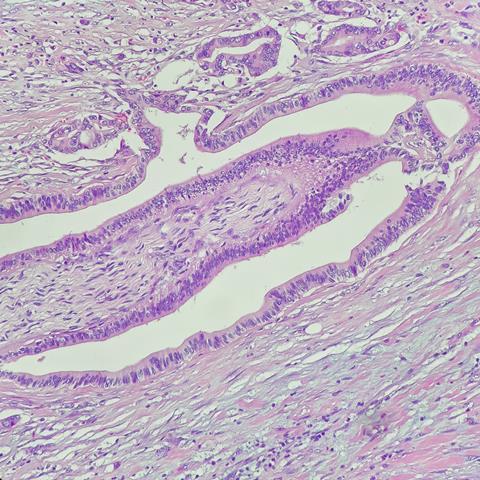

Cholangiocarcinoma is a rare cancer of the liver, deriving from a malignant transformation of cholangiocytes, the cells lining the biliary tract.

The microfluidic chip is only a few centimetres in size. “Inside the device, in the micrometre channels realised using advanced photolithographic techniques, we seeded cancer cells sampled from patients affected by cholangiocarcinoma. The cells successfully reproduced the tumour architecture in vitro,” detailed Dr Rasponi.